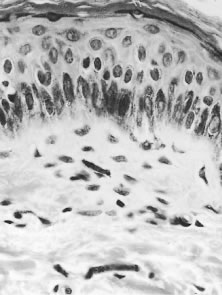

SKIN The earliest changes in the skin in onchocerciasis are mild and are often limited to a perivasculitis.14 In more heavily infected persons, microfilariae can be found, especially at the epidermal-dermal junction (Fig. 7). Live microfilariae are usually not surrounded by inflammatory cells. Later changes include hyperkeratosis, acanthosis, and parakeratosis, with an increase in inflammation and fibrosis. Dermal collagen is disrupted by the deposition of increasing amounts of mucin ground substance and by fibrous scar tissue. With more advanced fibrosis and inflammation, microfilariae become less common in the superficial dermis and are found mainly in the deeper layers. Ultimately, the dermis becomes fibrotic and is covered by a thinned and atrophic epithelium. There are areas of depigmentation and hyperpigmentation (Fig. 8). Some patients have a much more severe, reactive onchodermatitis, often confined to one limb. This was first described in Yemen and is called “sowda,” or black limb. Here, the most prominent histologic change is an extensive infiltrate of plasma cells.14 Microfilariae are seen occasionally in the deep dermis or in skin snips. These patients have a high cellular immune response to onchocercal antigens, which is suppressed if their disease becomes generalized. NODULES Adult worms may at times be found free in fascial planes, although they are far more commonly encapsulated in nodules. Some nodules are palpable and visible, lying subcutaneously over bony prominences, especially the iliac crests, greater trochanters, ribs, knees, ankles, coccyx, and skull. Others, probably more numerous, lie deep and impalpable, attached to the fibrous capsules of joints (especially the hip joint) or close to the periosteum of bones or in intramuscular fasciae. Occasionally, nodules are found in even deeper structures such as intracranially or in the wall of the aorta. When examined microscopically, dense scar tissue surrounds and encases the adult worms, which are coiled up like a ball of string. Developing microfilariae can be found in the uteri of most female worms. Degenerative females often become calcified. Nodules may show an inflammatory infiltrate of varying intensity and occasionally areas of necrosis and liquefaction. THE EYE As in the skin, many of the changes in the front of the eye at least are related to invasion by, and local death of, microfilariae. The pathophysiology of chorioretinal disease is far less clear and may also be related to immune complex disease,12,15 the presence of antiretinal antibodies,16 or other mechanisms.17 Much of the chorioretinal disease seems to start at the level of the retinal pigment epithelium.18 Few eyes have been examined histopathologically, and most of these have had end-stage disease that often obscures the earlier changes.19 Live microfilariae cause little intraocular reaction and may be found in the conjunctive, cornea, posterior sclera, anterior and posterior chambers, vitreous, uveal tract, inner retina, and optic nerve and its sheath. OTHER TISSUES Microfilariae have been found in many of the deeper organs, including the liver, kidney, spleen, pancreas, lung, peripheral nerves, and arteries. They have also been found in tears, blood, urine, cerebrospinal fluid, sputum, vaginal secretions, and peritoneal fluid. |